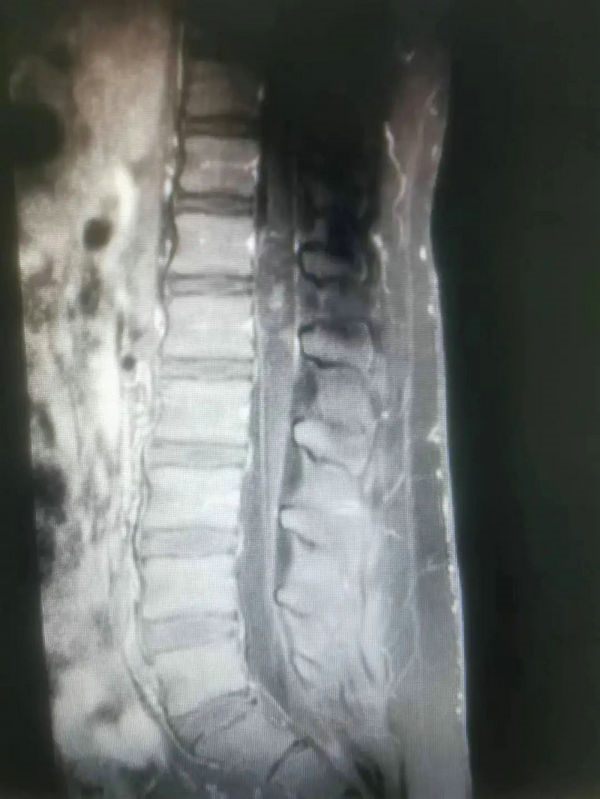

次日凌晨,在当地医院救护车的护送下急诊转入郑州大学五附院,在CT室等相关科室协助下,连夜完成了MRI、CT等术前检查,磁共振提示患者腰椎脊髓内肿瘤占位,并存在出血可能,病情棘手且凶险,单单从影像学很难彻底明确病变性质,不管是单纯的出血或者恶性肿瘤出血,亦或者良性病变,如果继续压迫脊髓,患者可能终生大小便失禁和下半身瘫痪状态。同患者父母沟通病情后,患者父母一时无法接受,告诉医护人员,孩子学习在当地全县名列前茅,如果以后瘫痪在床,孩子可能无法接受。作为医护人员,一边安慰患者父母和患儿,一边积极完善术前准备。

寿记新科主任、王建业副主任医师、高海东主治医师等科室医护人员紧急讨论病情后,制定了详细的手术救治方案后,在医院麻醉科、神经电生理等科室协作下紧急为患者进行了神经显微镜下“脊髓内肿瘤切除术”。经过医护共同努力,术后患者双下肢运动功能即刻恢复,可自主抬起双腿,经过术后治疗和康复锻炼,患者已逐渐恢复排便排尿功能,术后病理证实,占位为室管膜瘤合并肿瘤卒中,后续进一步治疗也在进行中,患者及家属对郑州大学五附院神经外科医护团队高度称赞,并送来锦旗对医护人员表示感谢。